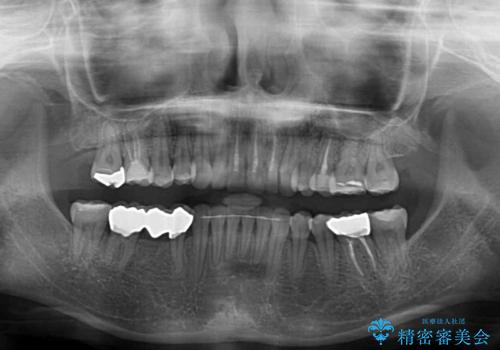

- 上下前歯のデコボコと奥歯の欠損を気にして来院された患者様です。

右下の欠損分は奥歯が倒れ込んでスペースがなくなっていたため、矯正治療により本来の位置に歯を移動させ、オールセラミックブリッジによる欠損補綴治療を行うこととしました。

全顎的にセラミッククラウンが多く装着されているため、インビザラインによる矯正治療を行うこととしました。

右下は移動量が多いため、十分な移動が達成されない場合はワイヤー装置を使用する予定としておりましたが、しっかりとマウスピースを装着してくださったため、前歯とともに十分に歯を動かすことができました。